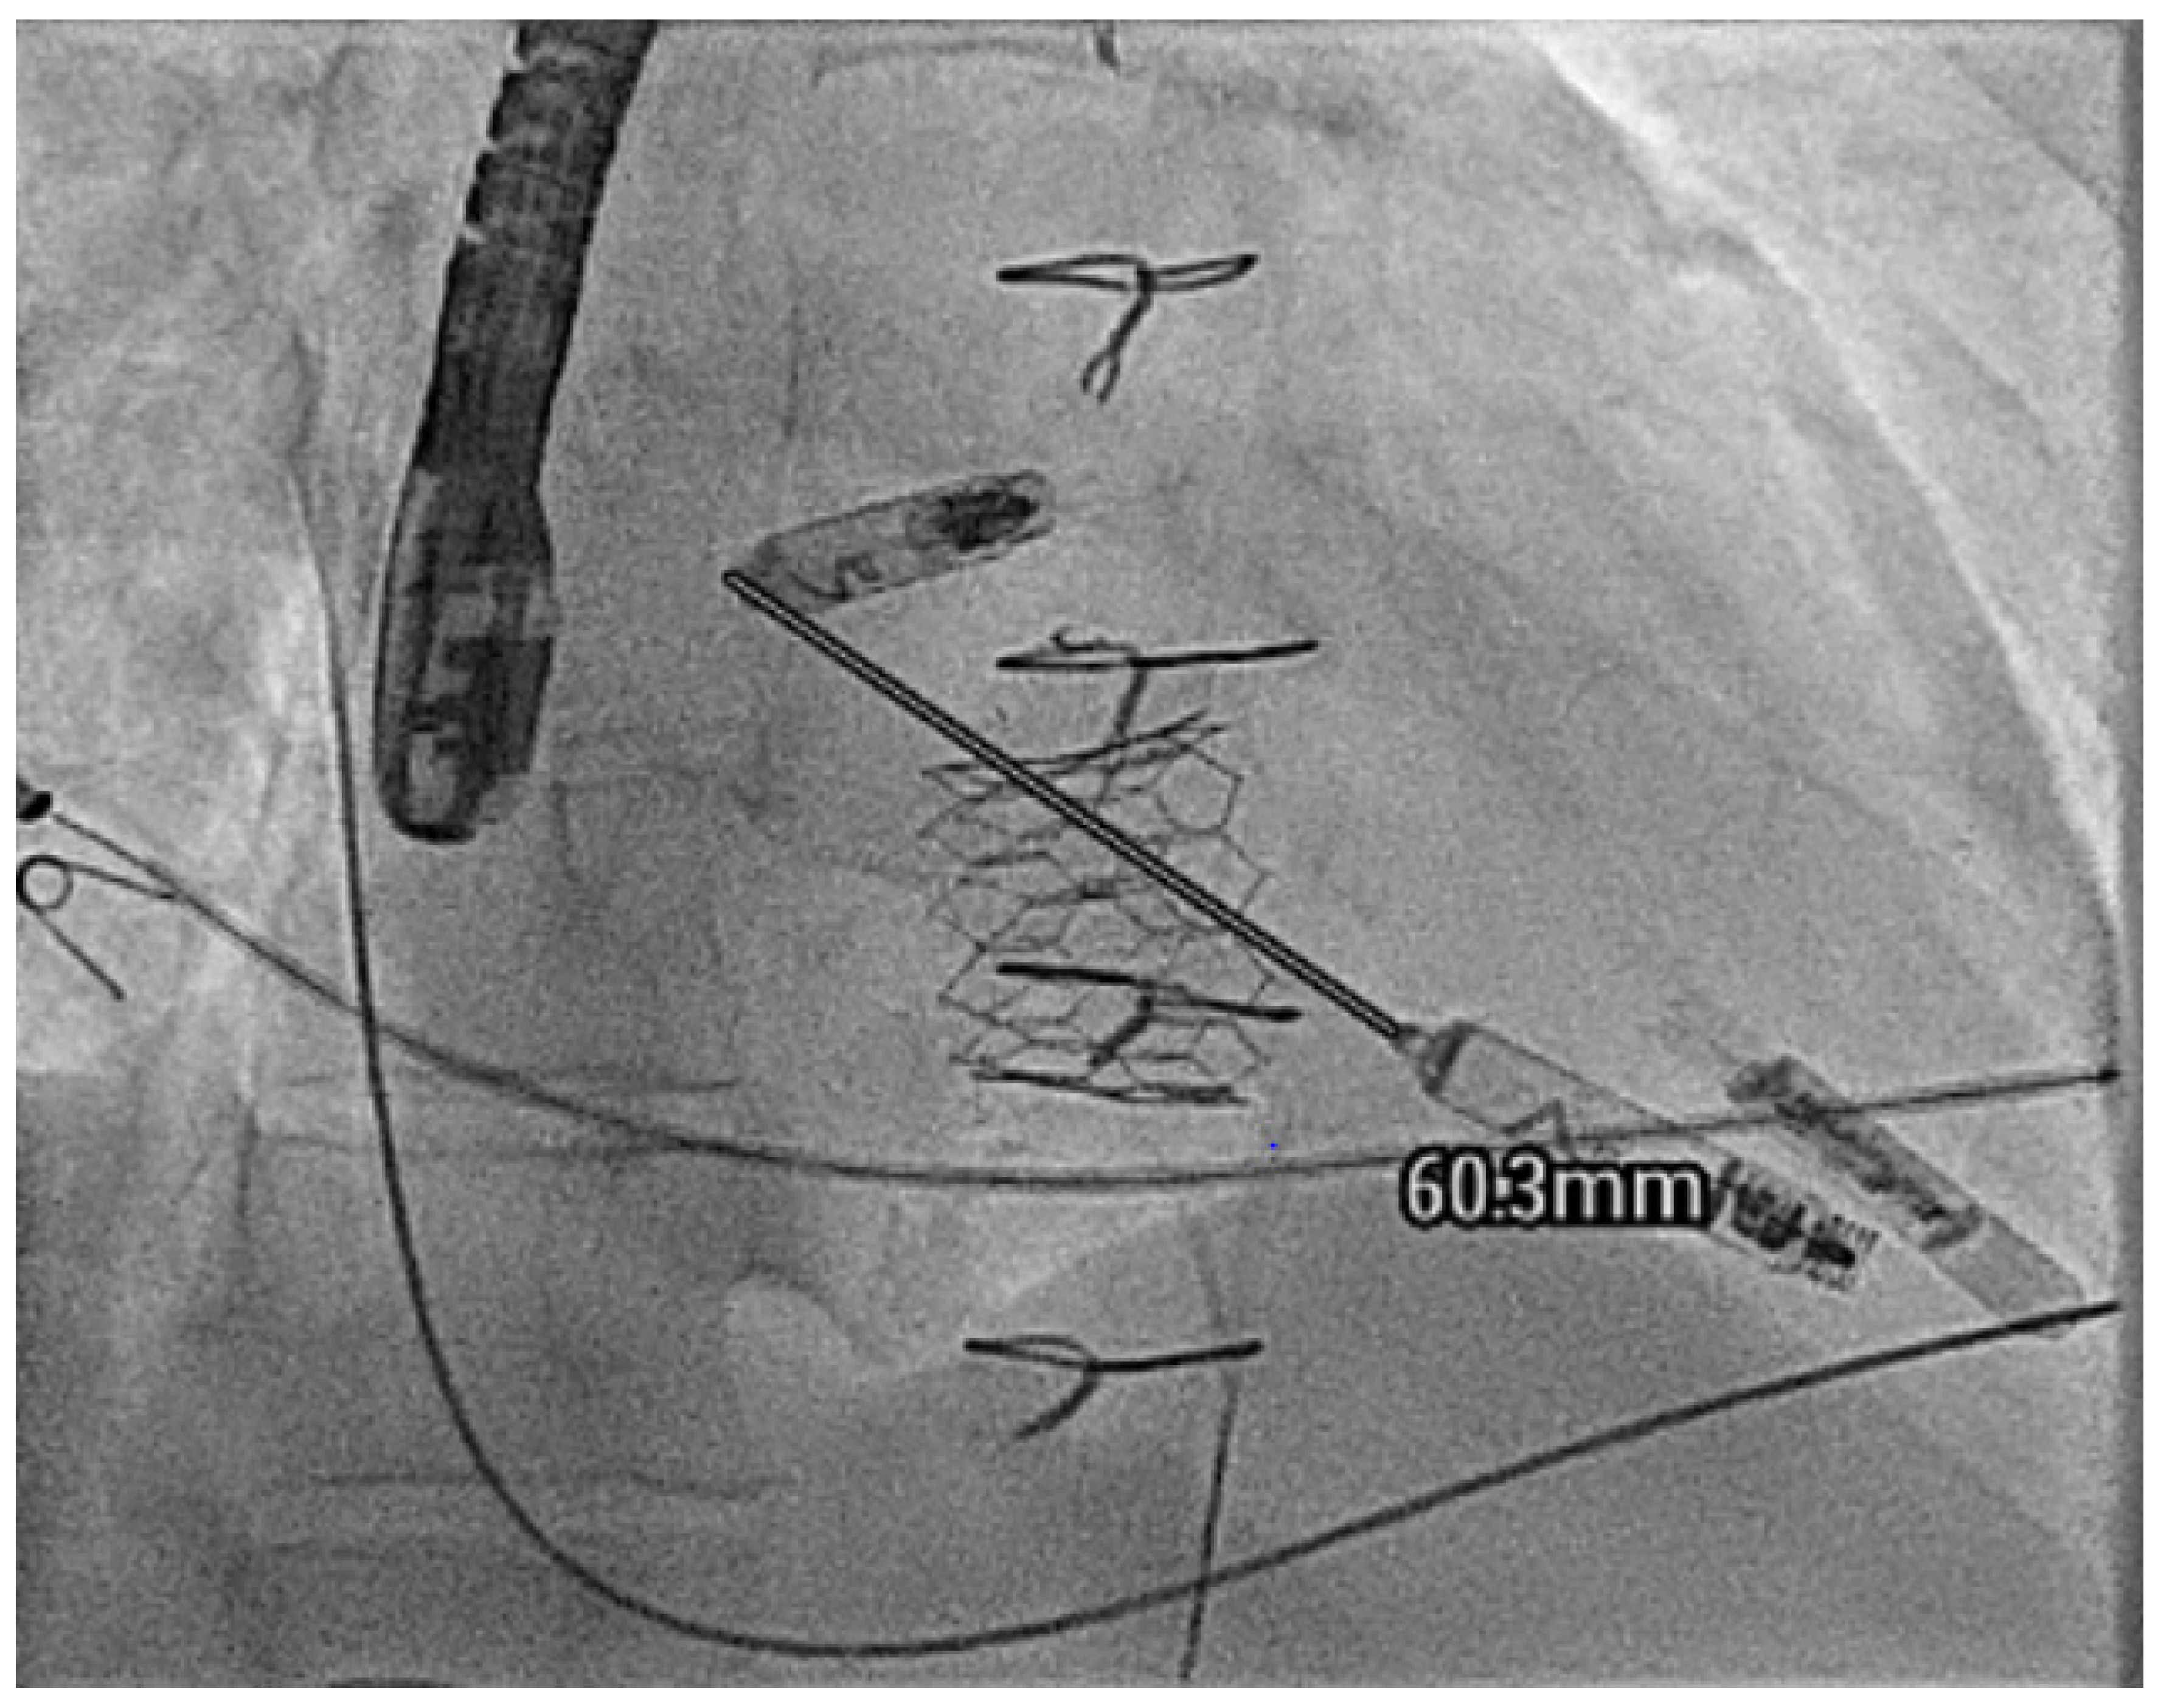

- Hayle, P.; Altayeb, F.; Hale, A.; Rao, A.; Ashrafi, R. Case report demonstrating novel approaches for leadless pacemaker implantation in the single ventricle heart. Eur. Heart J. Case Rep. 2025, 9, ytaf146. [Google Scholar] [CrossRef]

- Goulden, C.J.; Khanra, D.; Llewellyn, J.; Rao, A.; Evans, A.; Ashrafi, R. Novel approaches for leadless pacemaker implantation in the extra-cardiac Fontan cohort: Options to avoid leaded systems or epicardial pacing. J. Cardiovasc. Electrophysiol. 2023, 34, 2386–2392. [Google Scholar] [CrossRef]